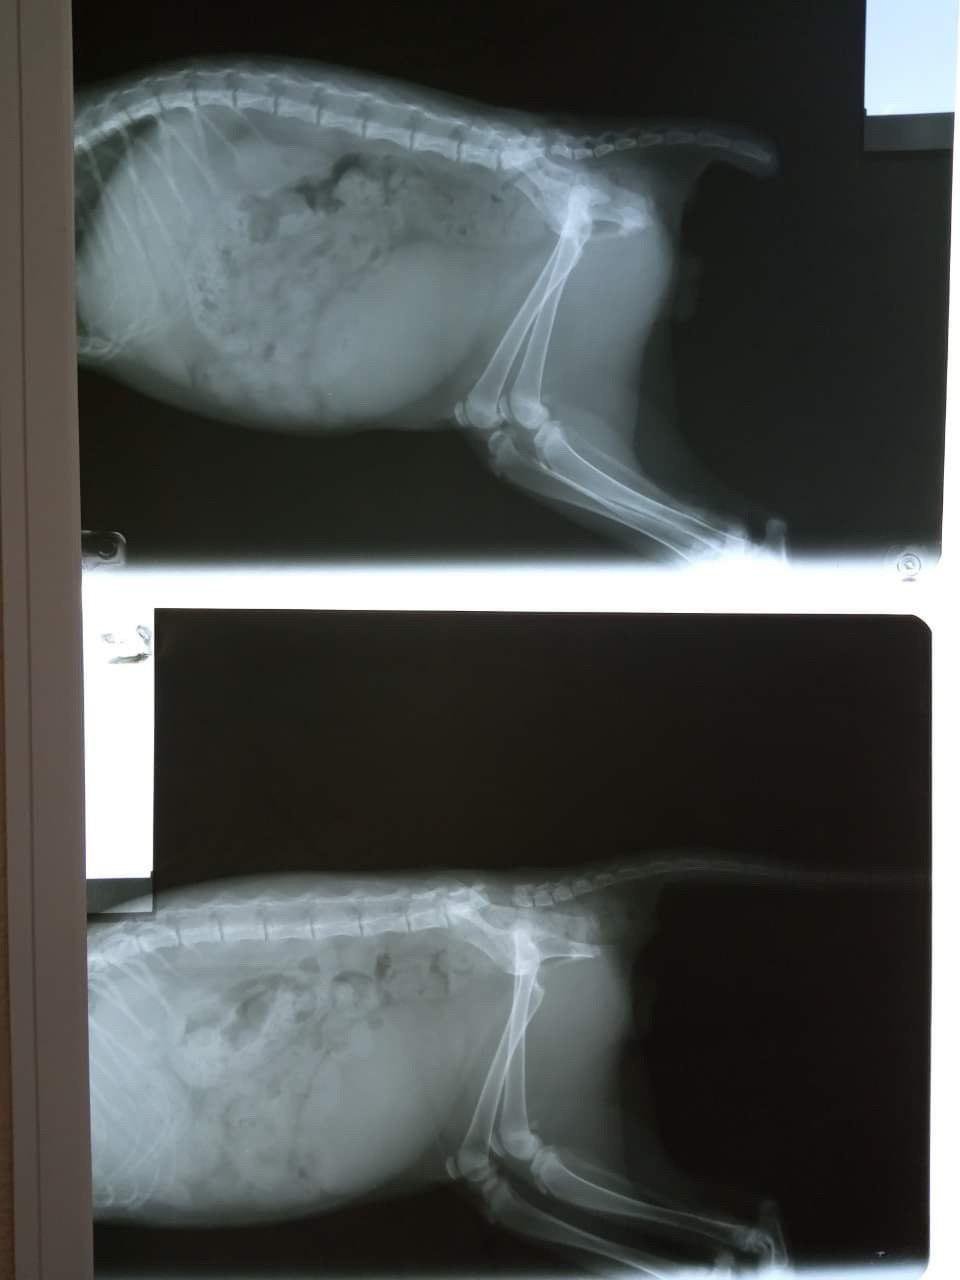

"Повреждение спинного мозга. Нарушение иннервации сакральной области позвоночника. Перелом хвостового соединения в области крестца. Как сильно нужно было тянуть малыша Савелия за хвост, чтобы разорвать позвоночник. Малыша выкинули в мусорный бак, его заметила дворник. Котенок не писает сам, самопроизвольно какает. Прямо на осмотре из котенка вышел целый комок целлофановых пакетов. Возможна интоксикация и гибель. Малыш срочно едет на операцию (в долг). Операция будет стоить минимум 2 500 + стационар от 650 гривен в день, потом обычный стационар и лечение.